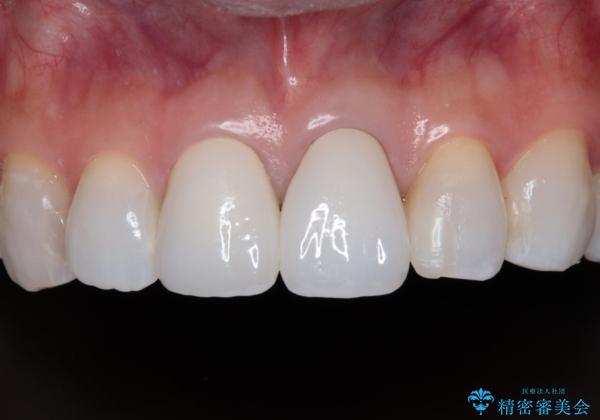

元々の歯の色が非常に白く、セラミッククラウンの色調を合わせるのに苦労しましたが、最終的に大変満足いただけるクラウンを装着することができました。